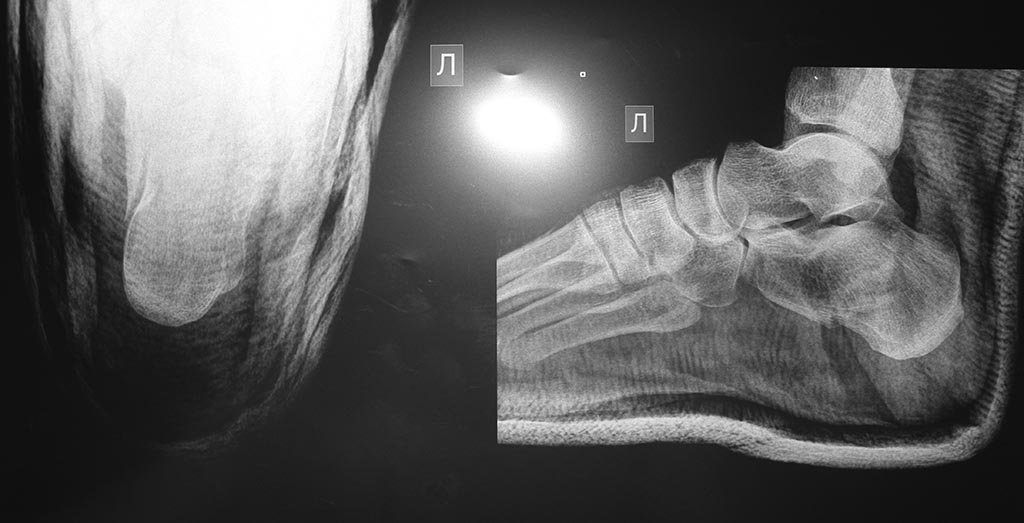

16.07.2015 был перелом левой пяточной кости с незначительным смещением. прилагаемый снимок сделан 20.07.2015 перед наложением гипса.

В больнице сказали категорически консервативное лечение. Проконсультировался еще с несколькими специалистами: 50% за операцию и 50% против. Причем те, кто против, против категорически, "ни в коем случае". те, кто за, угрожают в случае консервативного лечения проблемами при реабилитации и болями в будущем, невозможностью бегать и прыгать, ранний артроз. Те же, кто против, считают, что смещение минимально, проблем от операции может быть ОЧЕНЬ много, вплоть до остеомиелита, кость без операции будет после восстановления почти, как "до", проблем с бегом даже не будет. Подскажите, пожалуйста, чем обусловлены в данном случае обе точки зрения, и каково Ваше мнение?

Чем обусловлены разные взгляды - это слишком много рассказывать. Действительно, при таком положении фрагментов шансы, что все будет приемлемо, высокие. КТ надо сделать на всякий случай.